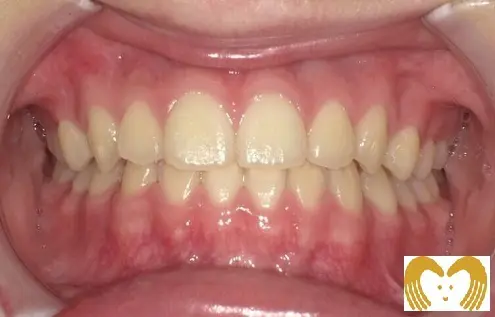

症例02:交叉咬合

《Before》

《After》

- 年齢:

- 7~12歳

- 性別:

- 女の子

- 治療内容:

- ネオキャップシステムによる、交叉咬合の治療

- 治療回数・期間:

- 約5年間

- 治療費:

- 495,000円(税込)

- リスク:

- 取り外し可能な装置の為、治療の効果が使用頻度に左右されます。